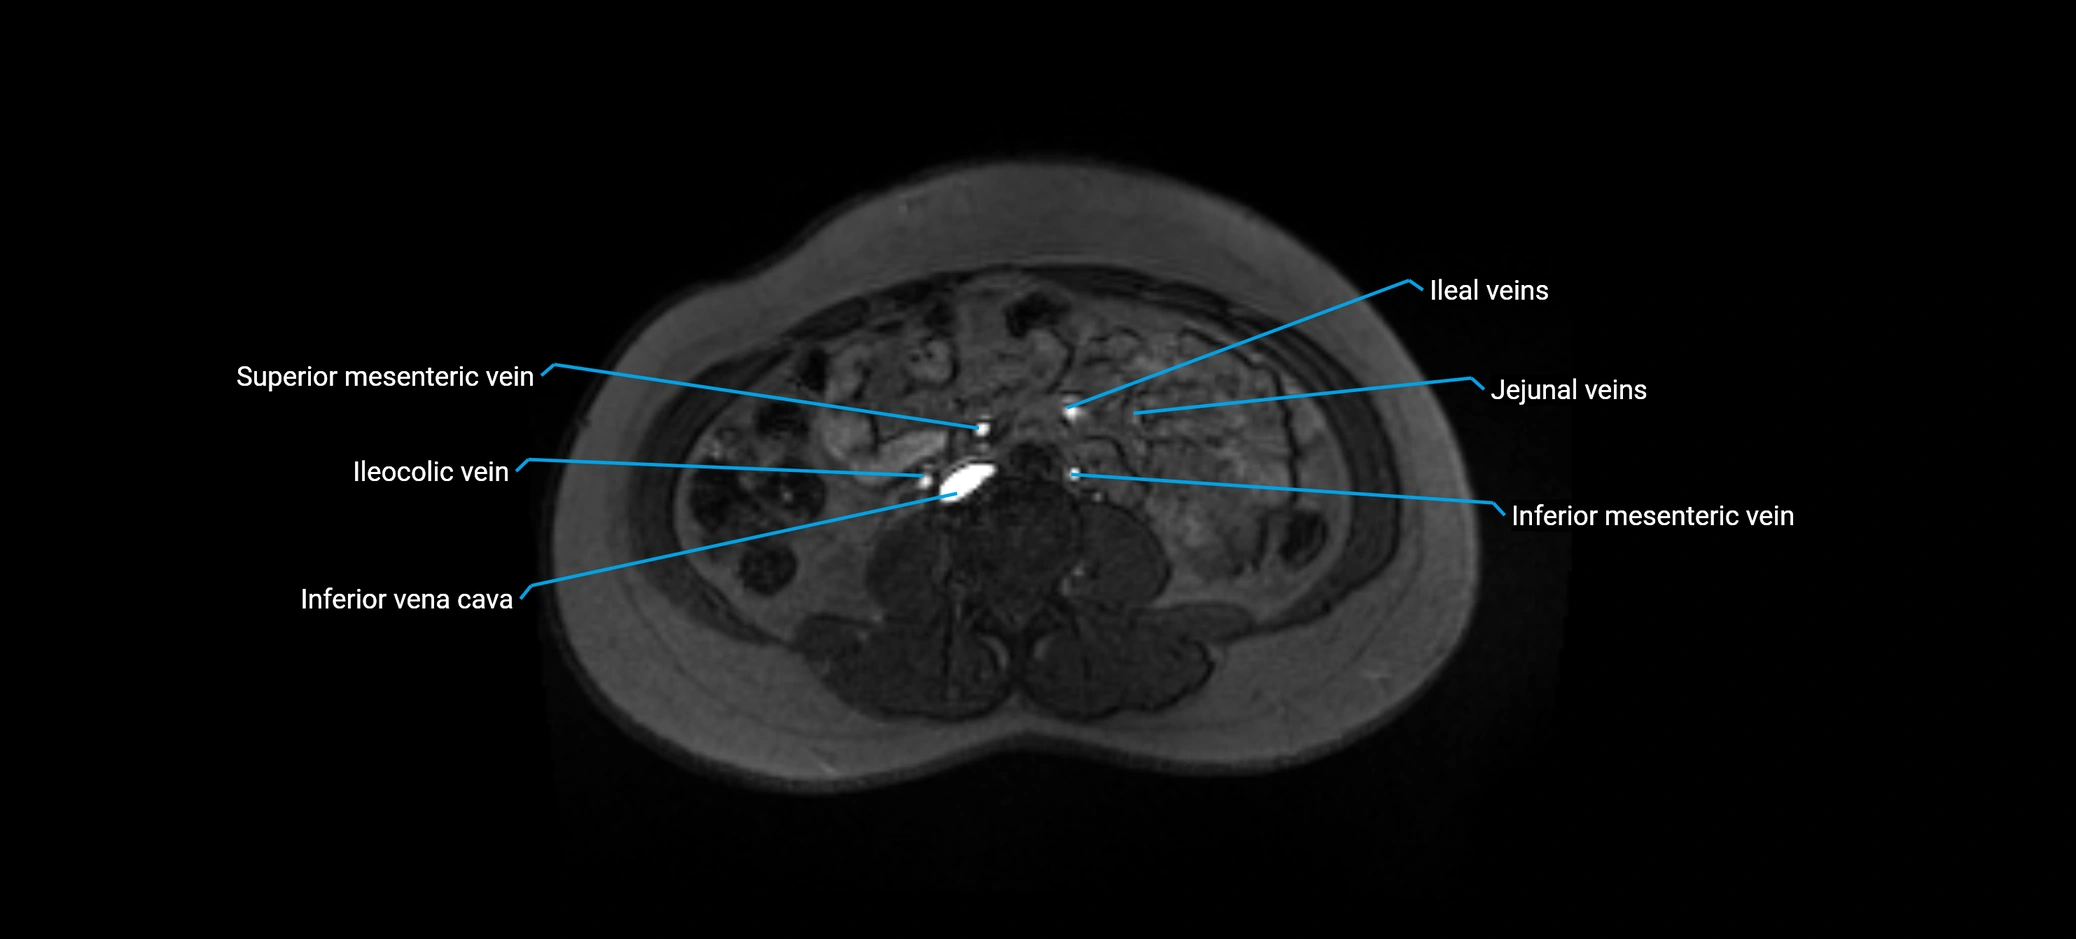

MRI image

image